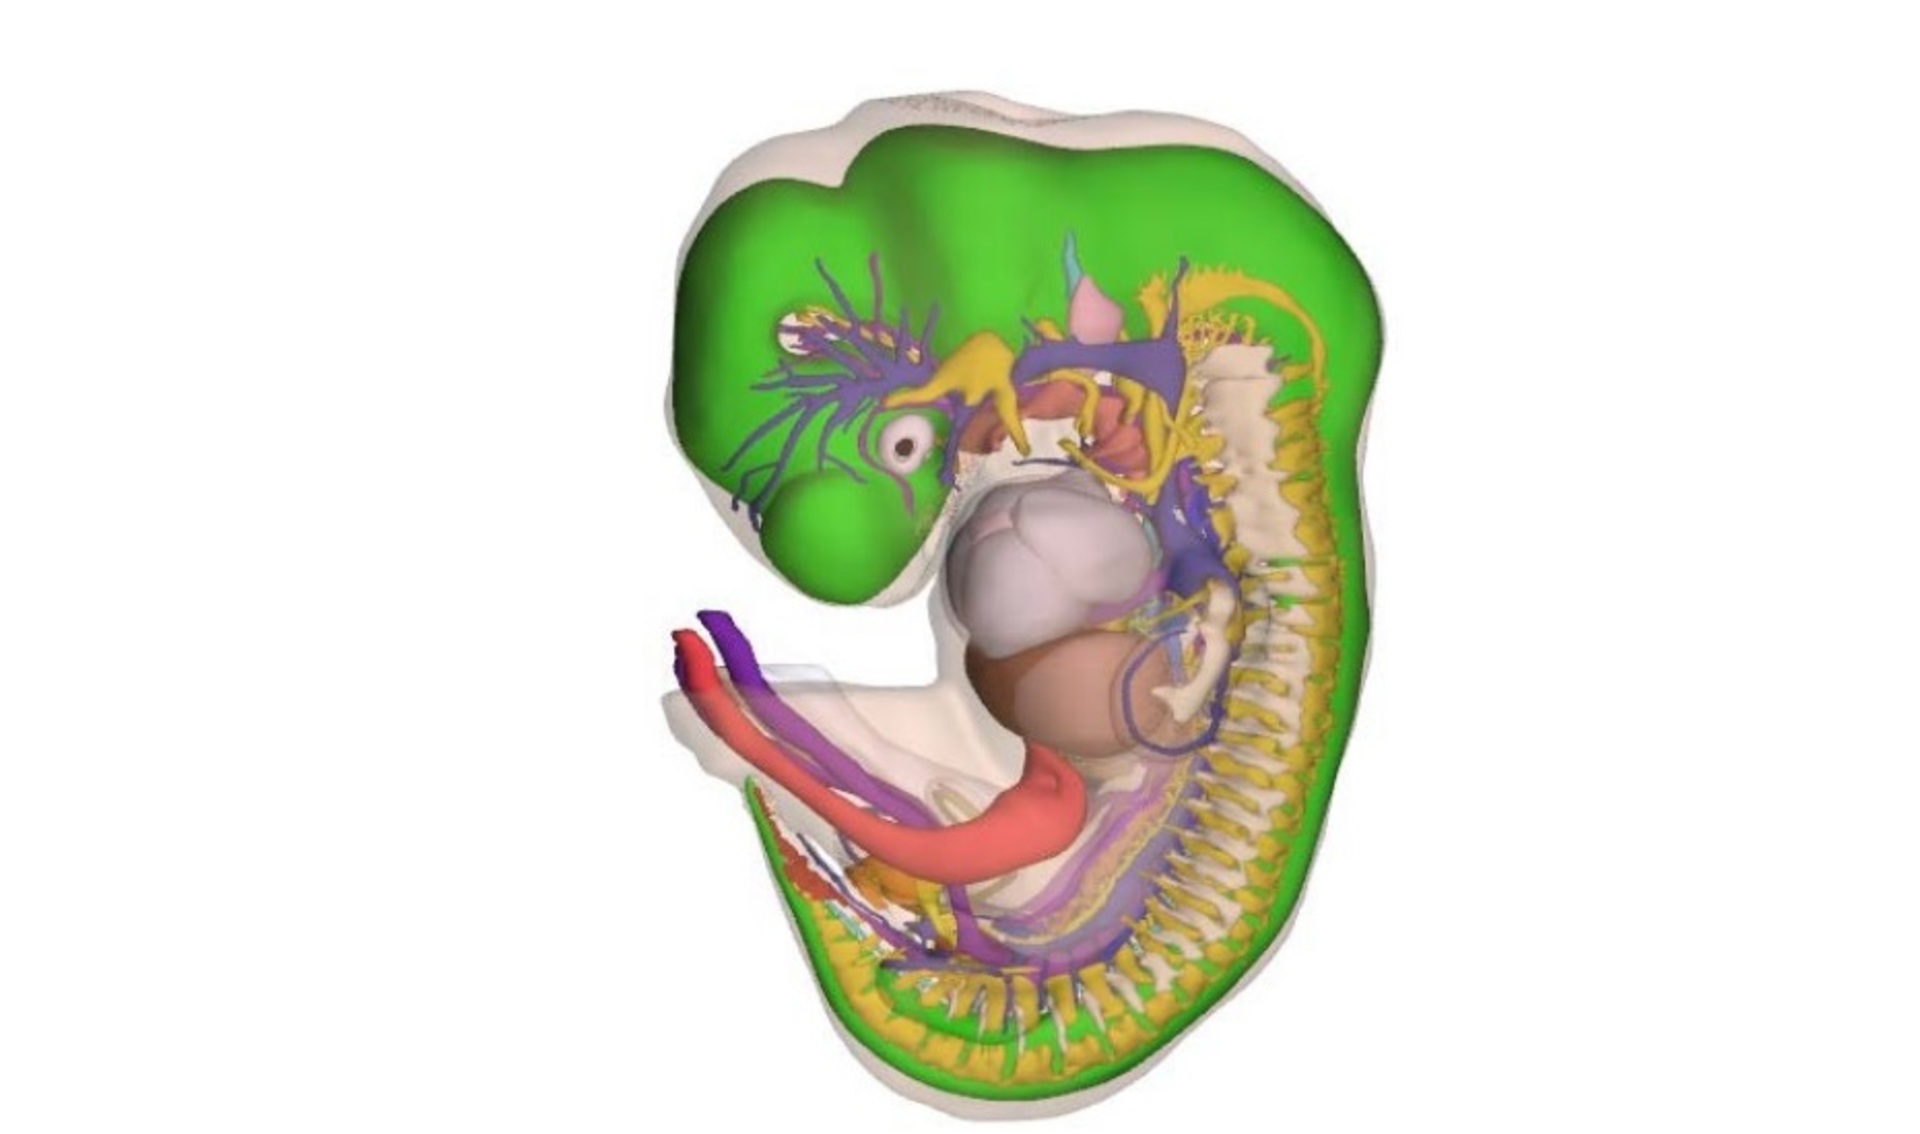

Ученые Академического медицинского центра в Амстердаме идентифицировали и промаркировала 150 структур и органов тела эмбрионов, после чего реконструировали их трехмерные компьютерные модели.

Все модели были классифицированы по стадиям развития и превращены в интерактивный формат 3D-PDF, который находится в свободном доступе.

Атлас позволяет рассмотреть как эмбрион в целом, так и его отдельные структуры, органы и системы.

Как отмечается, работа над созданием атласа велась с 2009 года. Участие в ней приняла группа эмбриологов при содействии 75 студентов.